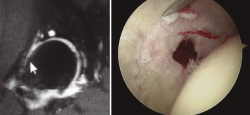

Radiológicamente, estos pacientes en los que podría considerarse un manejo artroscópico se engloban en la displasia de tipo A de Hartofilakidis. Debemos realizar radiología simple anteroposterior de pelvis, axial de Dunn, lateral pura y la proyección de falso perfil de Lequesne. Los ángulos a evaluar serían, de forma básica, el ángulo de inclinación acetabular (IA) o de Tönnis, así como el ángulo centro-borde lateral (CBL) o de Wiberg (Figura 5). En general, el ángulo de IA debe ser menor de 10°, mientras que el ángulo CBL debe ser mayor de 25°.

Figura 5. Medición de los ángulos centro-borde lateral, de 18,1° (Wiberg), y de inclinación acetabular, de 13,5° (Tönnis).

Respecto a las pruebas diagnósticas necesarias para evaluar a estos pacientes, la radiología simple con anteroposterior de pelvis y axial de caderas se postula como la base de las pruebas diagnósticas para la medición de los ángulos de cobertura. El falso perfil de Lequesne se debe realizar sistemáticamente para valorar la cobertura anterior. La realización de artro-RM es la mejor alternativa para la evaluación del labrum y la unión condrolabral, donde suelen verse en estos pacientes quistes paralabrales. Especialmente importante es la realización de TC con reconstrucción 3D en aquellos pacientes con osteotomías femorales o acetabulares previas en la infancia (Figura 6). La valoración de la anteversión femoral es muy importante y debe medirse con TC o resonancia realizando cortes al nivel de los cóndilos femorales.

Figura 6. Reconstrucción 3D de tomografía computarizada en displasia de cadera con descobertura anterior.